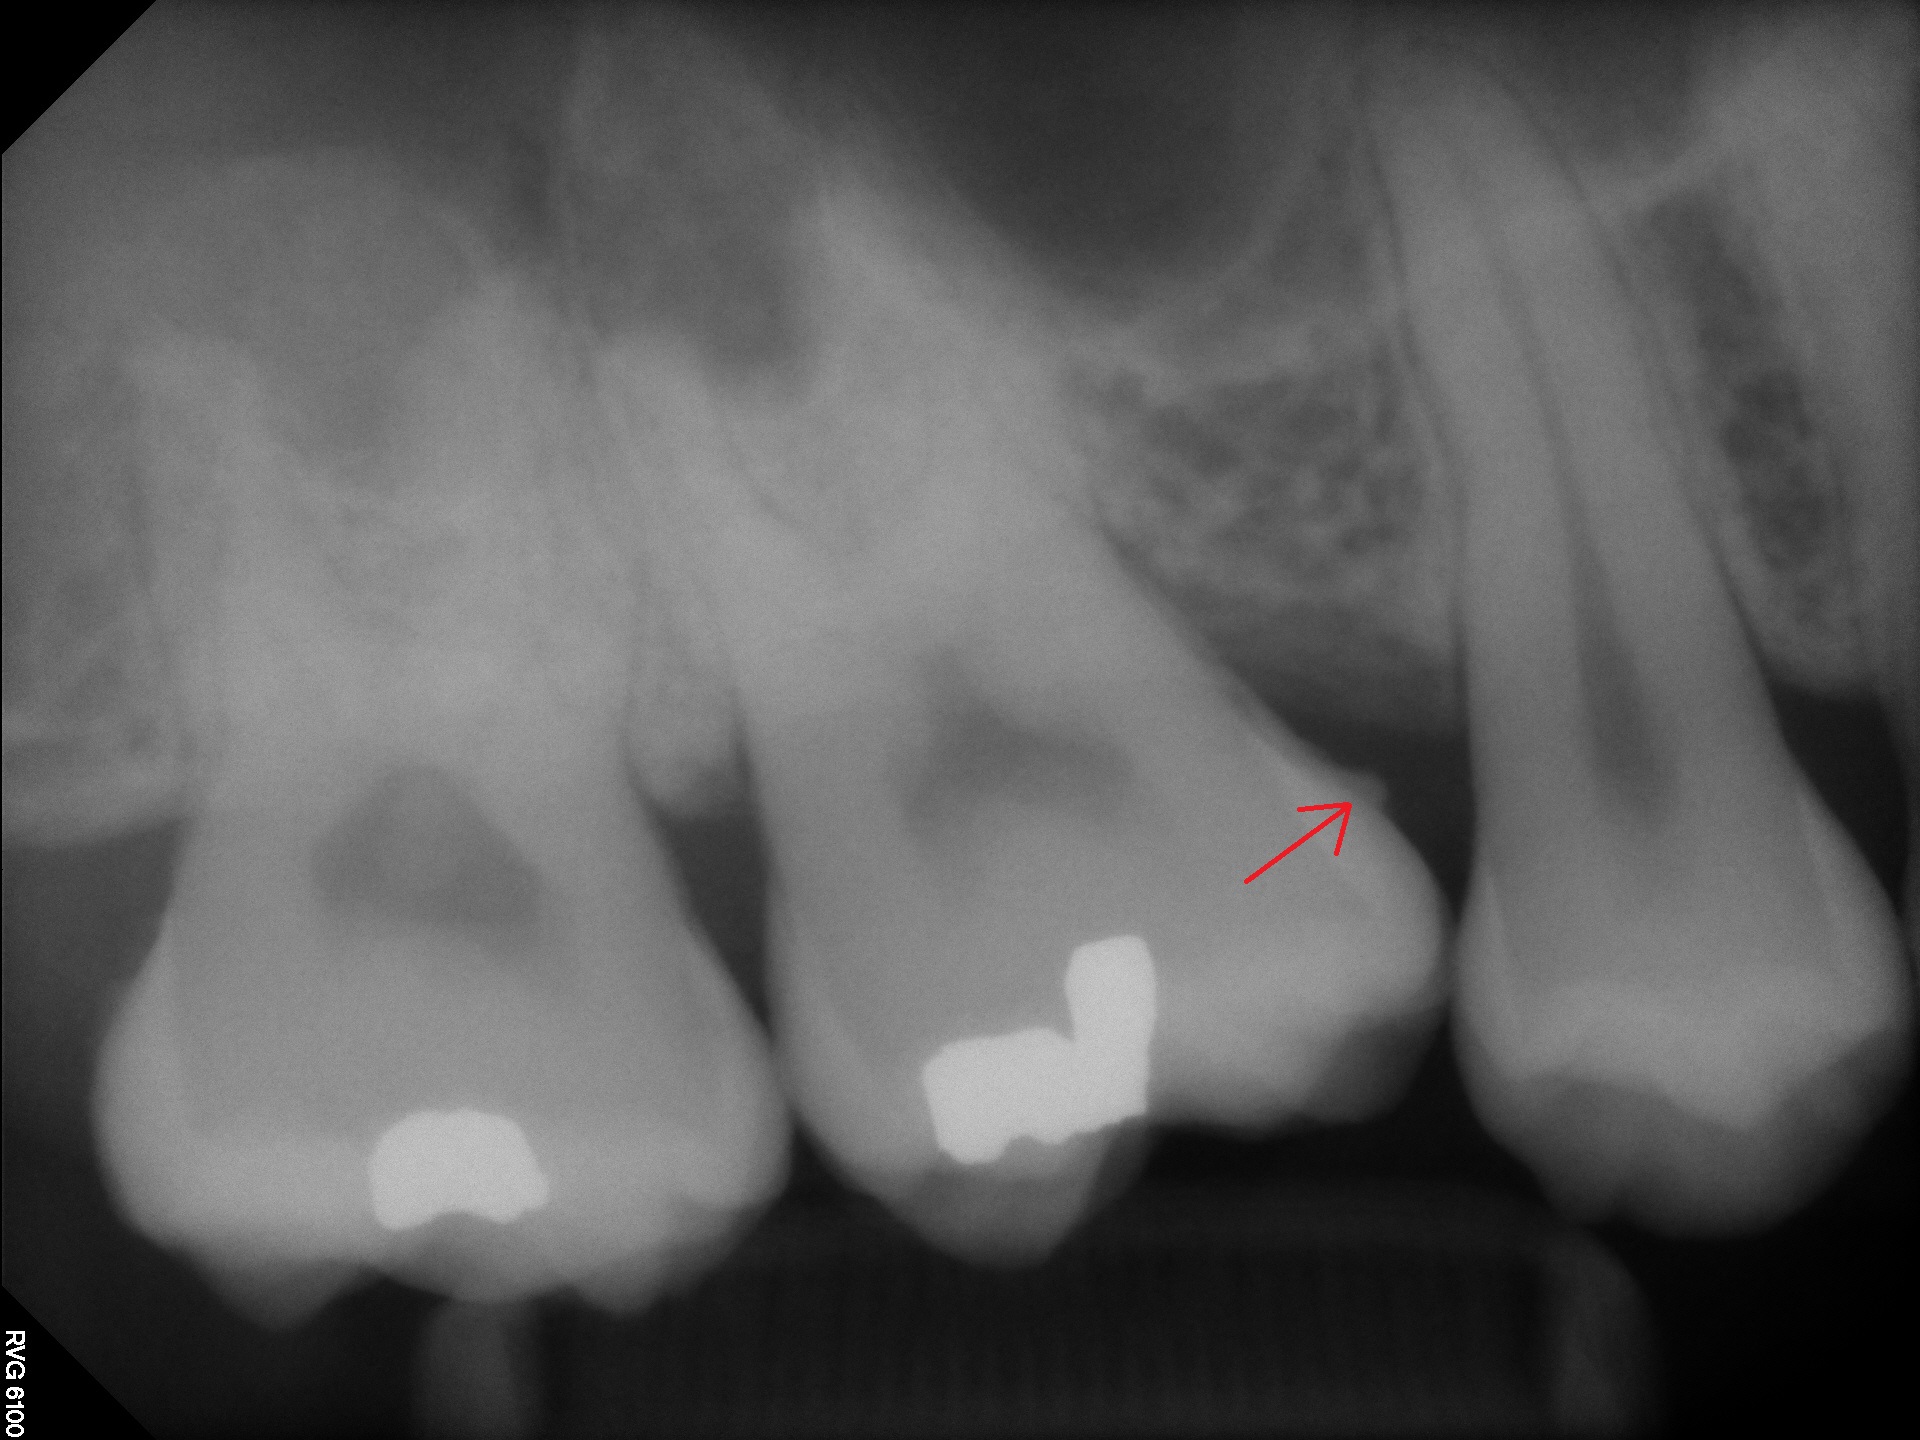

Digital RVG X-rays

Digital radiography is a form of X-ray imaging, where digital X-ray sensors are used instead of traditional photographic film. Advantages include time efficiency through bypassing chemical processing and the ability to digitally transfer and enhance images. Also less radiation can be used to produce an image of similar contrast to conventional radiography. Instead of X-ray film, digital radiography uses a digital image capture device. This gives advantages of immediate image preview and availability; elimination of costly film processing steps; a wider dynamic range, which makes it more forgiving for over- and under-exposure; as well as the ability to apply special image processing techniques that enhance overall display of the image.